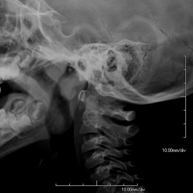

- Cavum X-ray

This technique uses X-ray rendered imaging for examining the cavum. Indicated for: respiratory distress, recurrent angina in infants and children.

This technique uses X-ray rendered imaging for examining the cavum. Indicated for: respiratory distress, regurgitation, recurrent otitis.